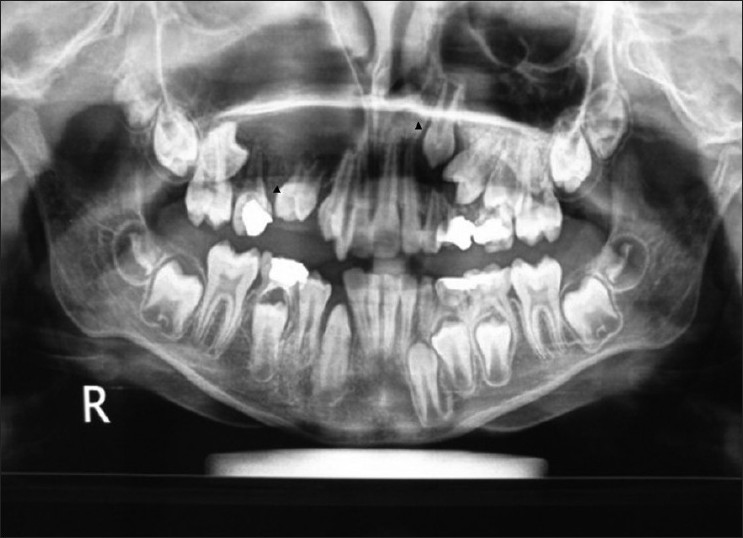

Gigi Atas Anak Tinggal Sedikit Akibat Karies Bolehkah Dicabut Halaman All Kompas Com